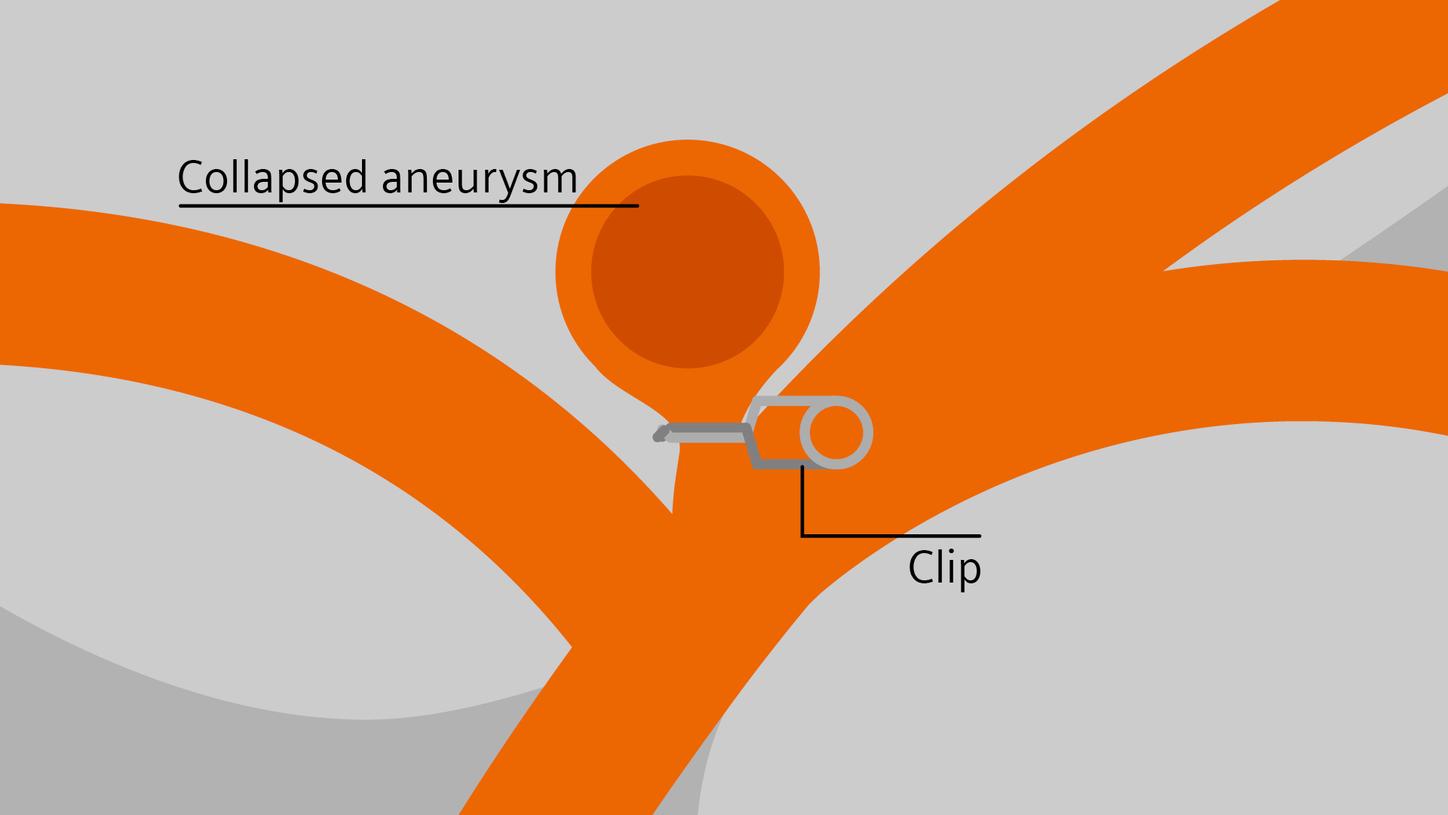

Treatment

In stroke care, time is brain. Rapid and accurate imaging is crucial to assess the extent of brain injury and guide immediate treatment. Angiography, MRI, CT, ultrasound, and lab diagnostics are essential tools in identifying stroke type, location, and severity. Advances in imaging technology now allow for even faster acquisition, improved resolution, and enhanced visualization of brain tissue and blood vessels. Innovations such as perfusion imaging, real-time vascular mapping, and AI-assisted diagnostics are transforming stroke workflows and enabling precise, timely interventions.